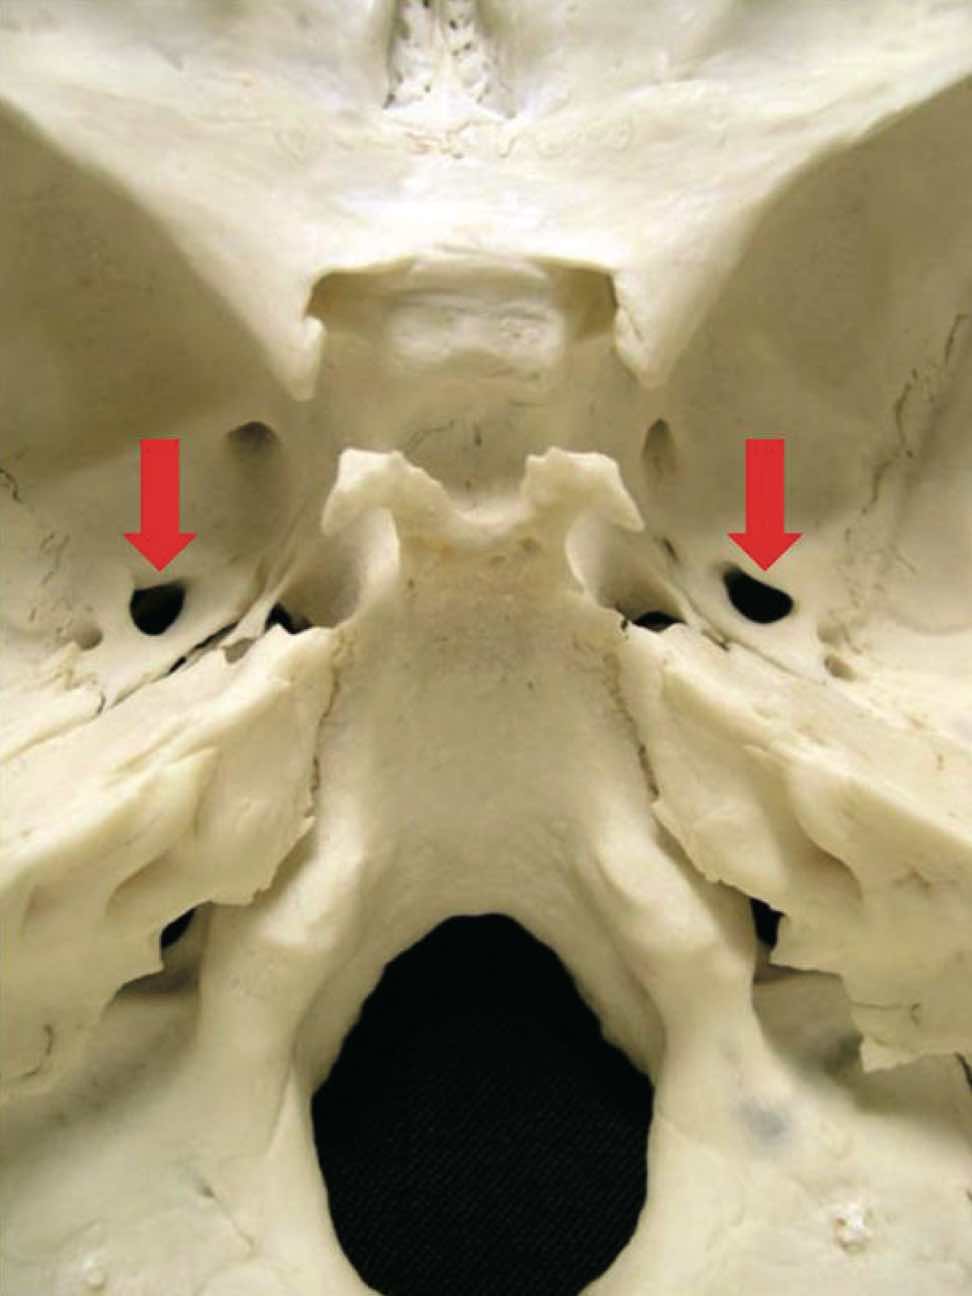

105C-112

内頭蓋底の写真を別に示す。矢印で示す孔を通過する神経が支配するのはどれか。2つ選べ。

1. 涙の分泌

2. 唾液の分泌

3. 咀囎筋の運動

4. 舌体部の味覚

5. 舌体部の触覚

スクリーンショット 2017 01 25 19 24 27

正答 3, 5

孔は卵円孔なので、V3 三叉神経の下顎神経が通ります。咀嚼筋の運動と、舌の知覚を担います。舌に関する味覚と知覚でややこしいので、やはりあの図を書いて、確実に選択肢を選んでいきましょう。